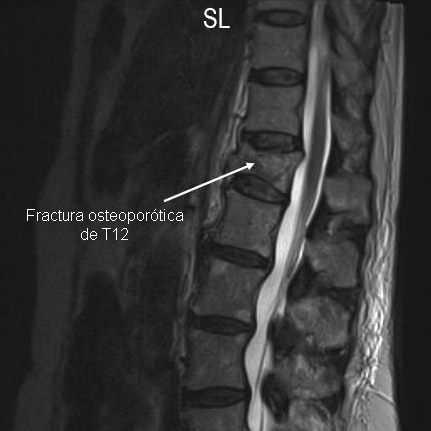

IRM de la columna lumbar: vista sagital (secuencia ponderada en T2) con fractura osteoporótica del cuerpo vertebral T12

De la colección personal del Dr. B. Nurboja y D. Choi